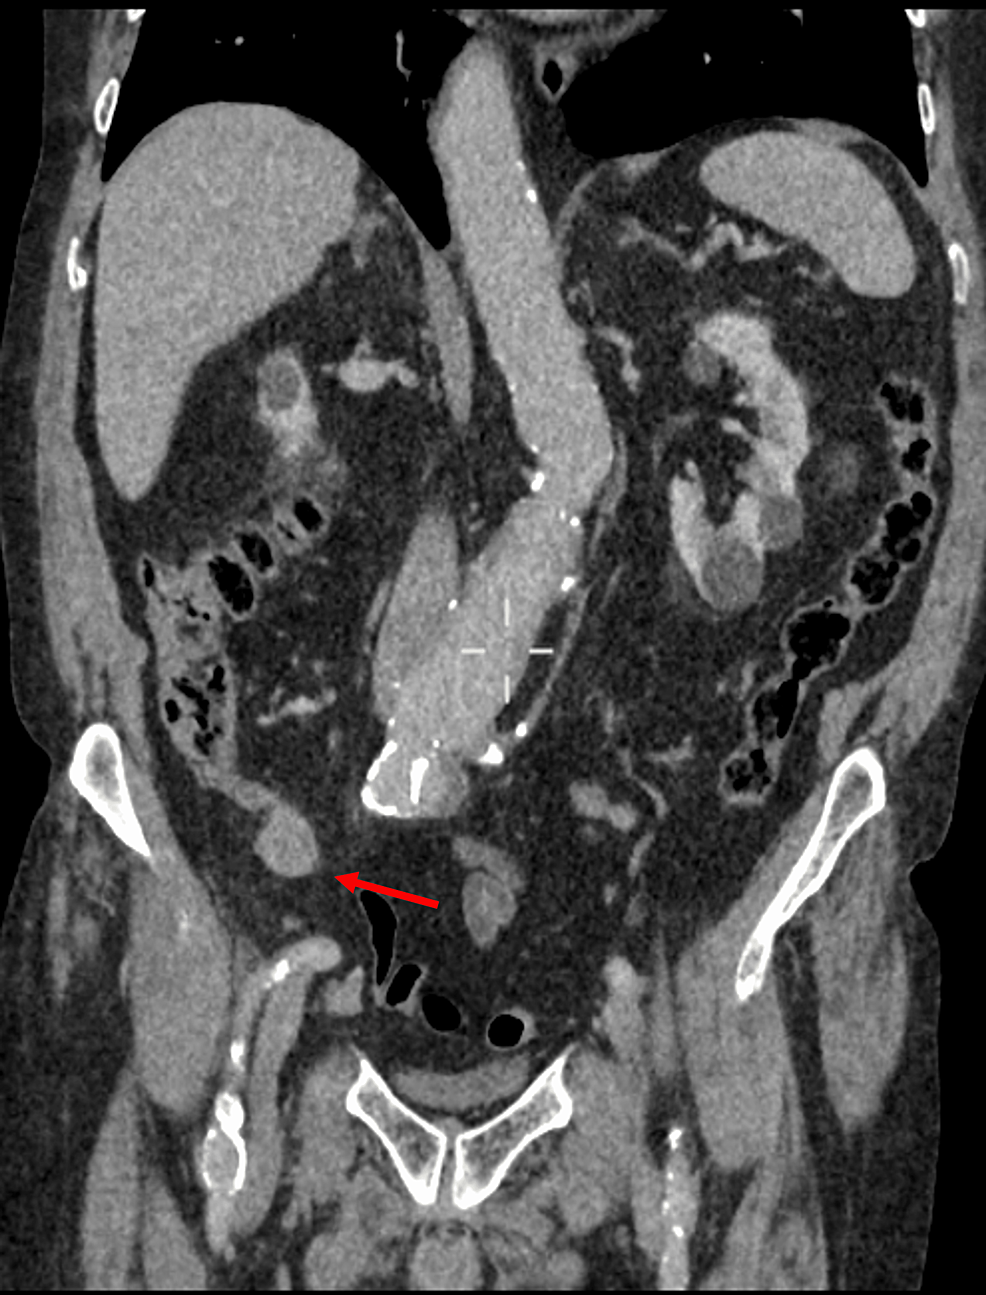

Απεικονιστικές εξετάσεις: Υπερηχογράφημα κοιλίας, και αν χρειαστεί, αξονική τομογραφία κοιλίας για επιβεβαίωση.

Η σκωληκοειδίτιδα είναι η φλεγμονή της σκωληκοειδούς απόφυσης, ενός μικρού τμηματος στην αρχή του παχέος εντέρου, που προκαλεί πόνο στην κάτω δεξιά κοιλιά, ναυτία, έμετο και πυρετό, απαιτεί άμεση χειρουργική αντιμετώπιση (σκωληκοειδεκτομή) για την αποφυγή σοβαρών επιπλοκών όπως η περιτονίτιδα, και συνήθως εμφανίζεται σε εφήβους και νεαρούς ενήλικες

Διάγνωση